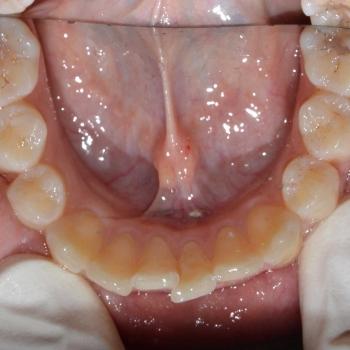

Eszter és édesanyja az iskolai fogorvosuk javaslatára kerestek fel, mert a kolléga, az esztétikai problémát okozó torlódás mellett, Angle II. osztályú funkciós eltérést is tapasztalt. Szerencsére ezeken felül egyéb eltérésre a konzultáció alkalmával sem derült fény.

Eszter a kezelés megkezdésekor headgear típusú fogszabályozó készüléket kapott annak érdekében, hogy a felső nagyőrlőket hátrafelé mozgassuk, illetve, hogy a keletkező rést felhasználjuk a kisőrlők és a szemfogak hátramozdítására is. Az így felszabadult hely az Eszter által választott hagyományos fém fogszabályozó segítségével felhasználható volt a metszőfogak elrendezéséhez, azok túlzott előredőlése nélkül.

A kezelés eredményeként minden kiindulási problémát sikerült megoldani és egy esztétikailag és funkcionálisan is szép mosolyt létrehoznunk.